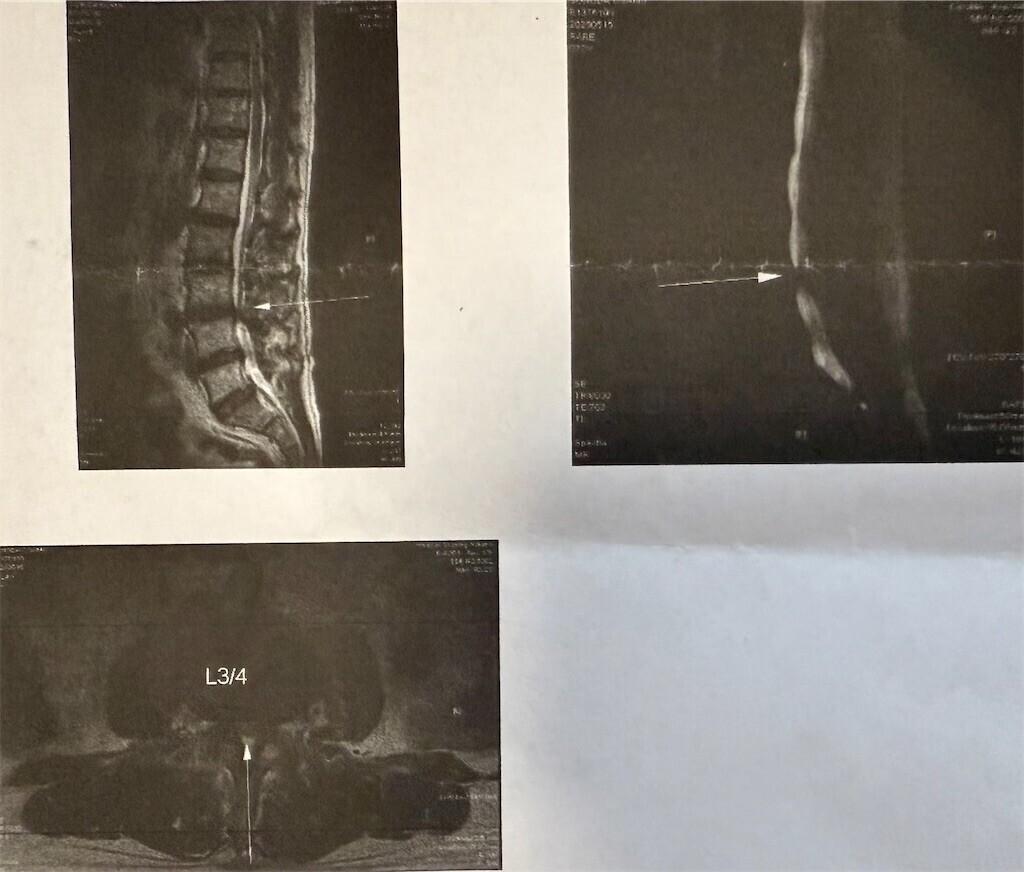

変形性腰椎症・腰椎椎間板症・脊柱管狭窄症が認められた

3時半過ぎにうちを出て、図書館に本を返却してから、整形外科に向かった。4時頃に整形外科に到着し、受付へ。10分ほど待って、呼ばれてリハビリ室へ。腰椎牽引マシンの椅子に座るように指示された。20分ほど牽引して、ちょっと待って、ベッドに移動し、理学療法を受けた。前回より柔らかくなっていると言われた。理学療法が終わって、待合室へ。15分ほど待って、診察室へ。先生の診断を受けた。リハビリの結果が良かったんですね?と言われた。コルセットをキャンセルしたので何か言われるかと思ったら、何も言われず。もうリハビリに来る必要はないとも。渡されたMRIの報告書には、「腰椎のアライメントは比較的保たれています。L1/2-L5/S1椎間板に変性・膨隆が目立ち、黄色靱帯や椎間間接の肥厚を伴って硬膜嚢を圧排しています。特にL3/4椎間板レベルで脊柱管狭窄が目立ちます。椎間孔は比較的保たれています。骨に異常信号域はありません。脊髄や馬尾に異常信号域はありせん。診断:変形性腰椎症・腰椎椎間板症があり、脊柱管狭窄症を認めます。」とあった。手術するなら、先生を紹介しますとも言われた。